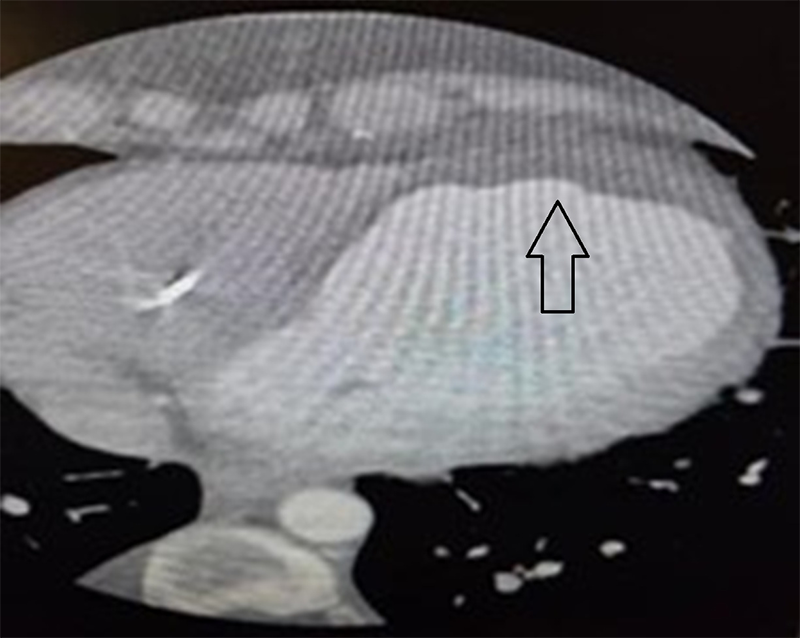

A patient in their thirties presented with chest pain, palpitations, and syncope, found to be in slow VT (figure 1). Past medical history included a late presenting large anterior wall myocardial infarction (MI) six months prior, heart failure with left ventricular ejection fraction (LVEF) 25%, left ventricular (LV) thrombus previously managed with apixaban, and a primary prevention implantable cardioverter-defibrillator (ICD). Multiple anti-arrhythmic agents, including beta blockers, amiodarone and lidocaine, failed, either due to side effects or lack of efficacy. Oral mexiletine was considered, but not used as intravenous lidocaine was not effective. ATP via the implanted ICD only very briefly restored sinus rhythm and was ineffective. Due to the presence of a large LV thrombus (figures 2 and 3) and, therefore, risk of stroke, synchronised cardioversion and acute VT ablation were not attempted. Laboratory work-up was entirely normal. This case highlights the challenges of managing refractory VT in a young patient with structural heart disease and limited procedural options.

In this patient, refractory VT persisted despite multiple antiarrhythmic therapies. The presence of a LV thrombus precluded catheter ablation as a treatment option, despite its organised appearance. The electrophysiology team advised against ablation due to the significant risk of thromboembolic complications, including stroke. Although cardioversion was recognised as carrying a high embolic risk given the well-formed thrombus, it remained a potential consideration in the event of clinical deterioration. Finally, combination therapy with high-dose bisoprolol and sotalol was utilised as a final attempt at medical therapy. This unusual combination proved to be efficacious and permitted safe discharge for a review at a specialist cardiac centre. As a result, heart transplantation was no longer considered following resolution of VT with this dual beta blocker therapy.